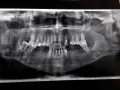

• У Вас отсутствуют 22, 24 зубы, на верхушках 23 имеется воспаление. Причина Ваших беспокойств связана именно с этим. Обратитесь к стоматологу на очный приём и продолжайте лечение.